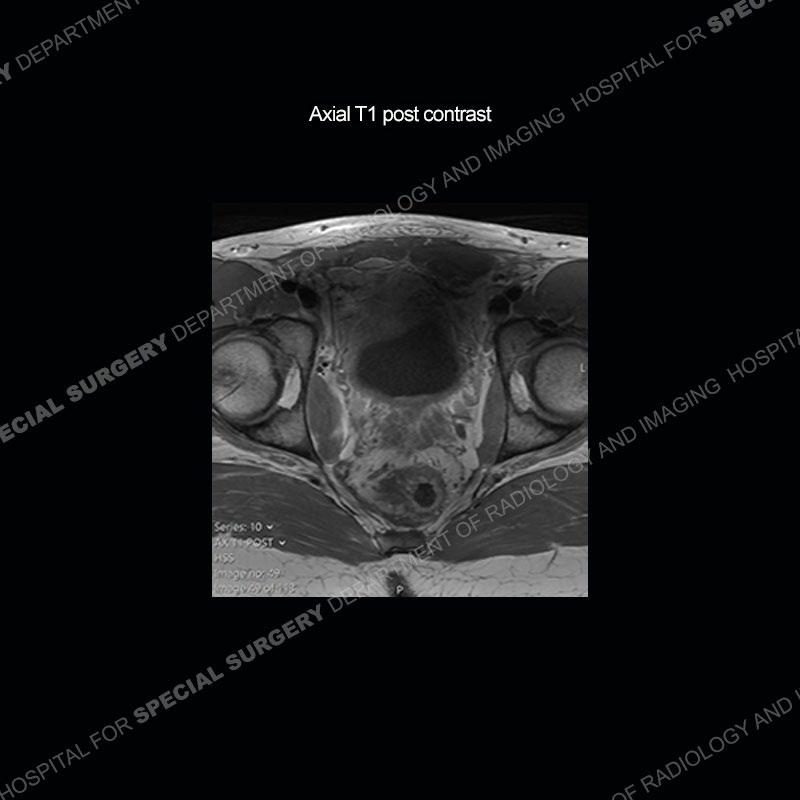

Subsequent MRI in a very short time interval shows markedly increased abnormality of the ramus and increased edema and “mass” of the soft tissue. Post contrast imaging shows multiple, rim enhancing collections of the soft tissue and similar albeit less conspicuous enhancing collection of the ramus.

Diagnosis: Osteomyelitis and Soft Tissue Abscess

The repeat MRI, with the marked degree of increased abnormality of the bone and soft tissue shifted the diagnosis to a high degree towards infection. Even the most aggressive of neoplasms would not have that the degree of change in a 3-day time span. The CT study was shown before the repeat MRI but actually occurred just after the repeat MRI. It helped confirm the destructive process of the ramus and particularly the abnormal architecture along the inferior margin. The patient went on to have a CT guided aspiration of one of the soft tissue collections with 4cc of purulent fluid obtained. A surgical irrigation and debridement of the bone and soft tissue was performed. A PICC line was placed and the patient is currently undergoing IV antibiotic treatment with a possible repeat irrigation and debridement.